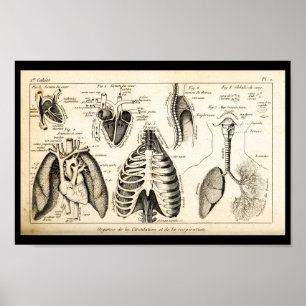

Human Internal Anatomy 1902 Print

Prijs€ 23,90